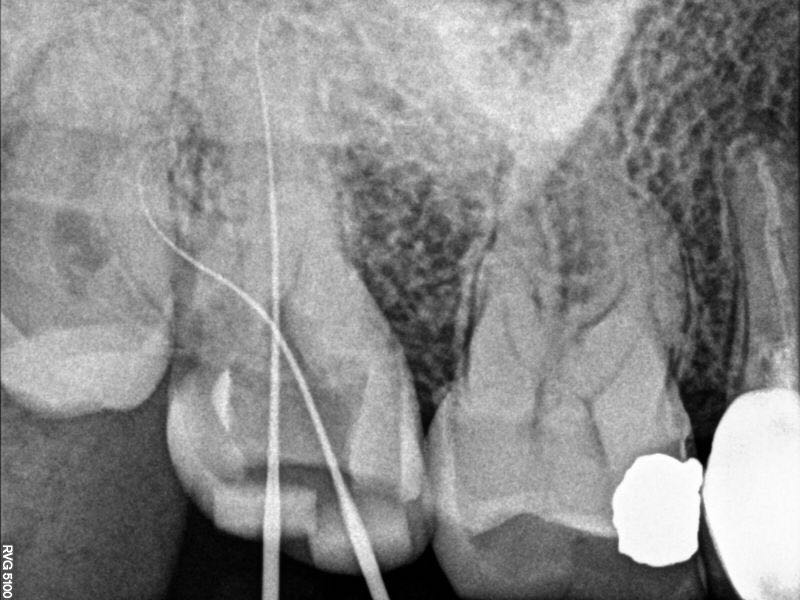

示踪片